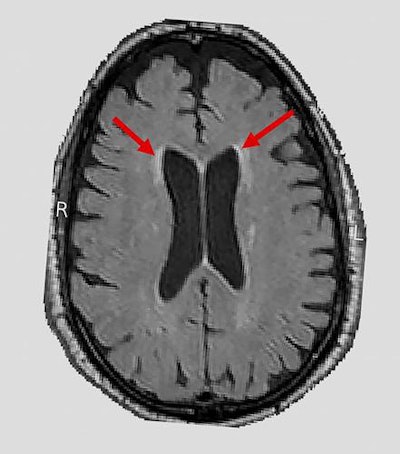

In the Systolic Blood Pressure Intervention Trial (SPRINT) Memory and Cognition in Decreased Hypertension (MIND) substudy, researchers used MRI to assess the effect of intensive blood pressure treatment on cerebral white-matter lesions and brain volumes in patients with hypertension. They found that targeting a systolic blood pressure (SBP) goal of less than 120 mmHg was associated with a smaller increase in cerebral white-matter lesion volume over the approximately four-year follow-up period, compared with the standard treatment goal of targeting an SBP of less than 140 mmHg (JAMA, August 13, 2019, Vol. 322:6, pp. 524-534).

SPRINT MIND researchers from 27 sites analyzed a subset of 449 hypertensive patients who received brain MRI at baseline and again approximately four years later. The group of patients who received intensive blood pressure management had an average increase in white-matter lesion volume of 0.92 cm3, compared with 1.45 cm3 in the standard blood pressure treatment group, the researchers reported.